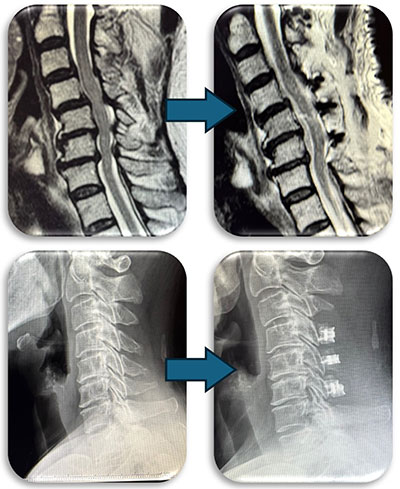

頚部の脊柱管狭窄症に対して、首の後ろから手術する椎弓形成術を行なった症例です。脊柱管と呼ばれる脊髄が通るトンネルの屋根部分にあたる椎弓を縦割し観音開きで広げ、さらに新しい屋根の代わりとなる金属プレートを被せることによって脊柱管を広げます。